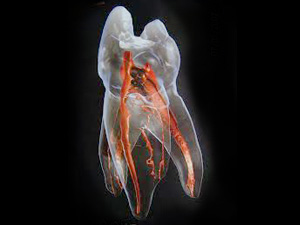

診断の正確さ:パーフォレーションの位置と大きさを特定する

修復の第一歩は、穴の正確な情報を把握することです。

肉眼や通常のレントゲンだけでは、根管の影に隠れて穴の位置を正確に特定することはできません。

歯科用顕微鏡(マイクロスコープ)

マイクロスコープを常時使用し、治療部位を最大20倍まで拡大します。

これにより、髪の毛ほどの小さな穿孔部位を直接確認し、穴の正確な大きさ、形、そして感染の状態を把握します。

歯科用CBCT(3次元レントゲン)

通常のレントゲンでは判別できない、穿孔部位と周囲の骨との位置関係、感染の広がりを立体的に解析します。

これにより、修復材を詰める深さや方向を正確に計画できます。